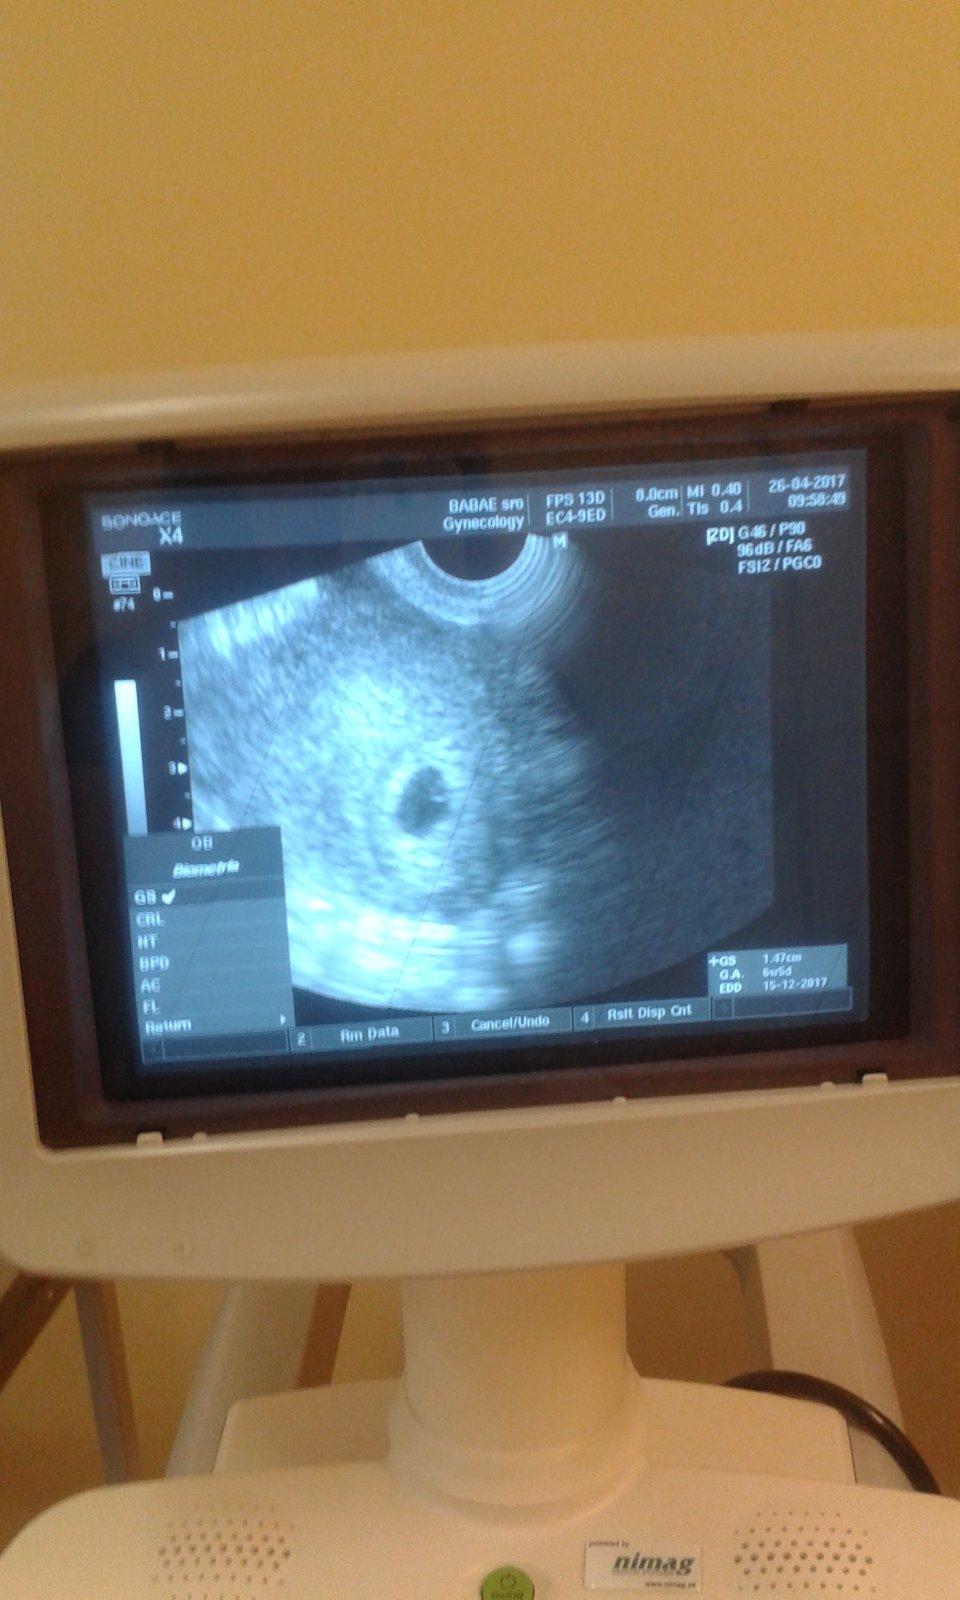

krv mi nebral este ze to az teraz ked dojdem..a srdiecko este nebilo ale babetko uz tam bolo lebo bolo vidiet v tom vaku malu bodecku ...🙂

@kotatko12345 tak ked si bola u lekara 26.4 bola si 6plua5 tak teraz budes ked som dobre pocitala tak 8 plus3 /9 tyzden ked dobre ratam tak malo byt bit srdiecko a velkost plodu od 14mm do 20 mm ..

@archanjel007 naposledy som bola 6+5tt a ano plod mal cca 20mm

@kotatko12345 to este len teraz bude mat babo 20mm v tom tyzdni bolo vidiet len bodku ako si vravela to mohlo mat od 5 mm do 13mm ja som bola 6plus4 /7 tyzden lekar mi povedal ze uz je tam akcia srdiecka a plod mam 7.7mm tebe to tak lekar nevysvetlil nezmeral si to ?

@archanjel007 no prvy krat co som tam bola povedal mi ze mam sliznicu moc vysoko ...druhy krat co som bola robil zase sono a potvrdil ze som tehu a spravila som si foto.a teraz idem 3x

@olylili tak to som zvedava ako podrastlo babo od 26.4